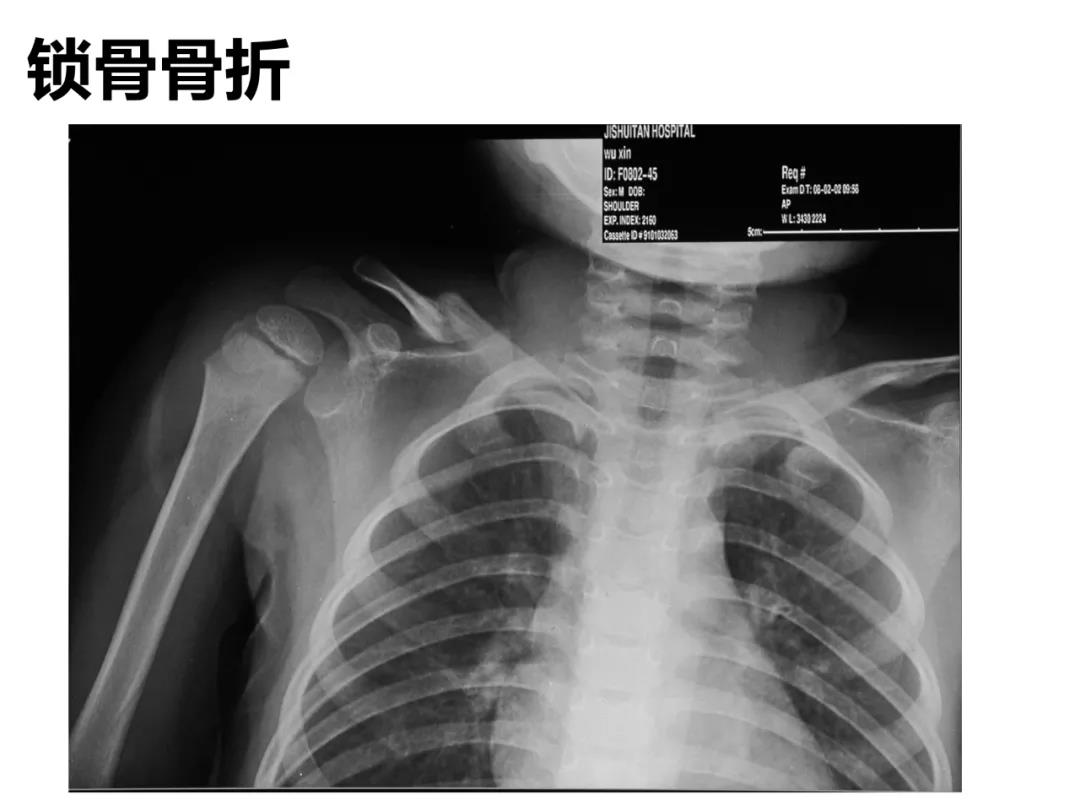

小儿骨科X线片汇总,临床读片宝典!